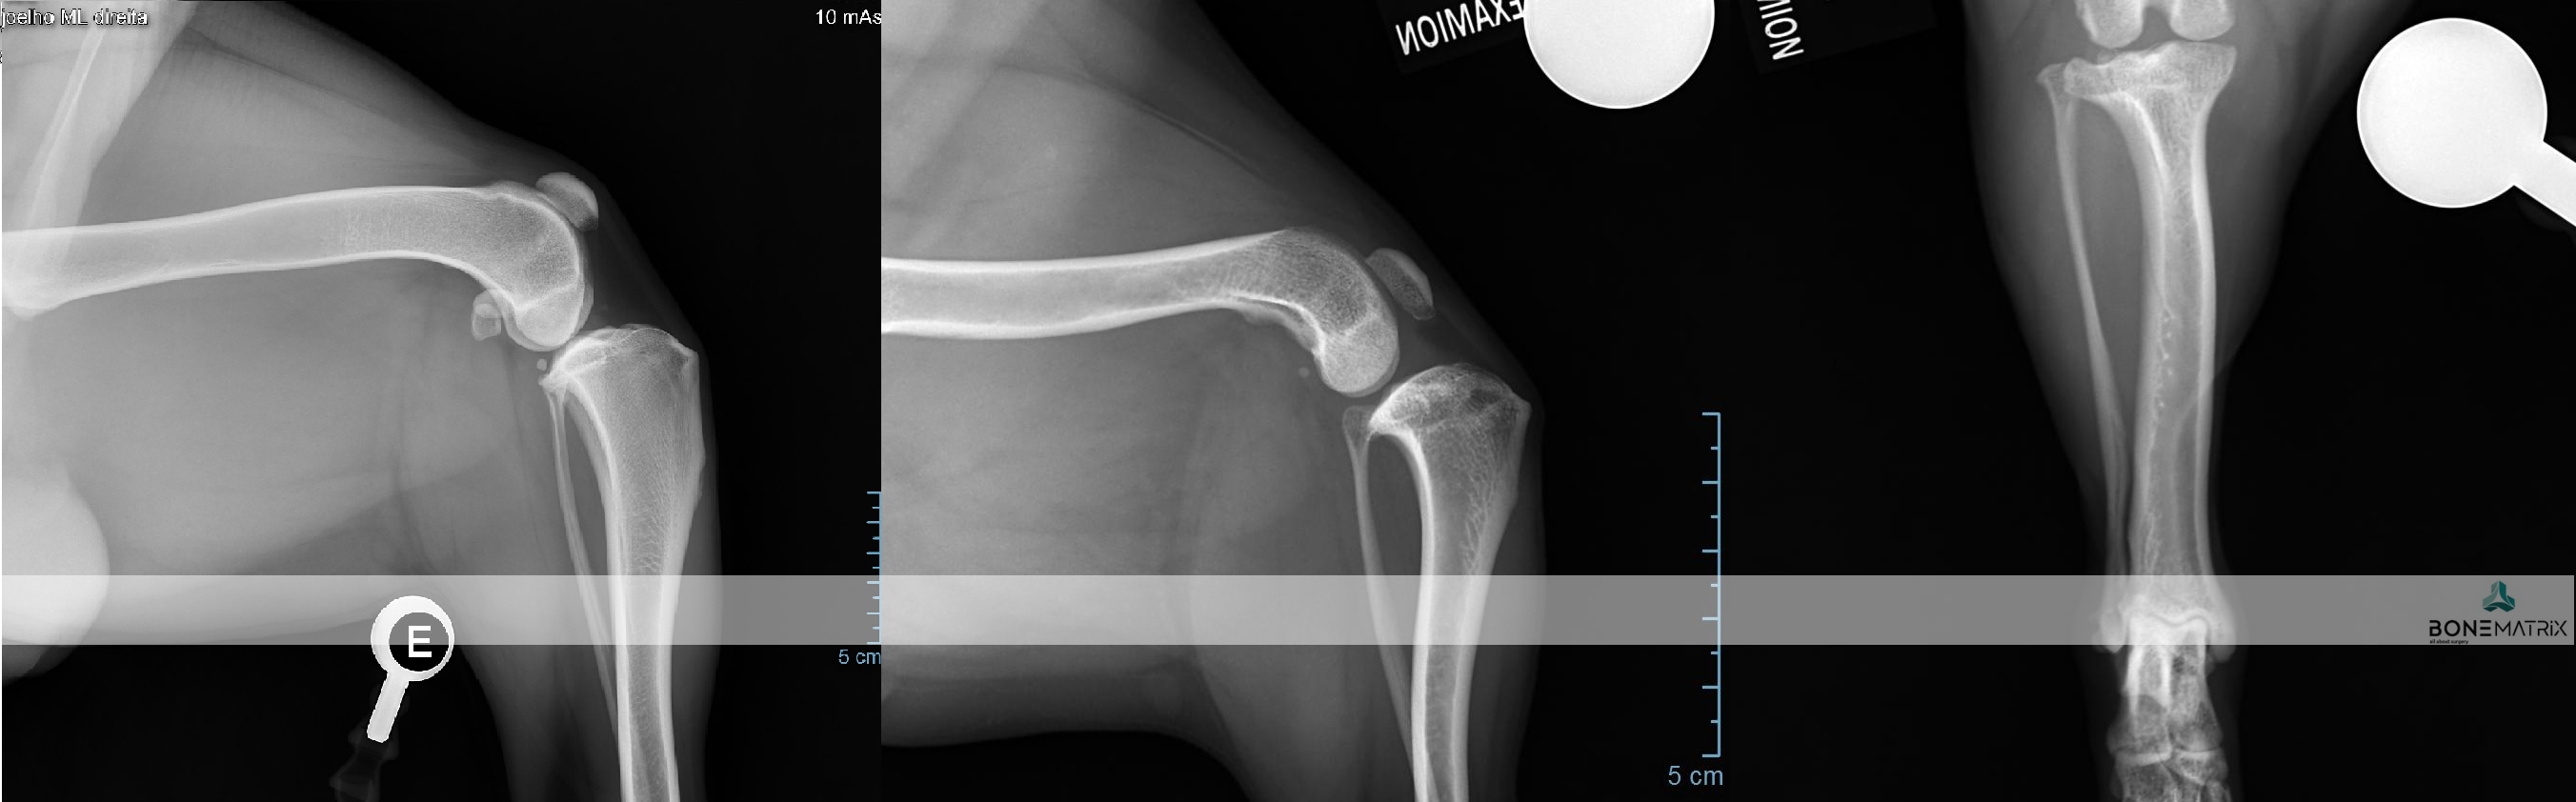

O que é?

A osteocondrite dissecante é uma condição que surge durante o crescimento devido a um distúrbio na diferenciação das células de cartilagem, o que resulta numa falha na ossificação endocondral (processo fundamental do desenvolvimento esquelético do feto e do cachorro em crescimento). Este defeito no crescimento resulta no aparecimento de um defeito ósseo tipicamente apresentado na cabeça do úmero, da qual se destaca um “flap” de cartilagem.

Como é feito o diagnóstico de OCD?

A suspeita surge quando se deteta claudicação, dor e desconforto no ombro, entre os 6 e 10 meses de idade. Alguns pacientes podem passar assintomáticos durante os primeiros anos, e mostrar desconforto numa fase mais avançada da doença e da idade. Após exame ortopédico, o diagnóstico é geralmente confirmado com um estudo radiográfico.

Situações mais subtis podem carecer de confirmação com estudo de TAC ou artrografia (radiografia com contraste articular).